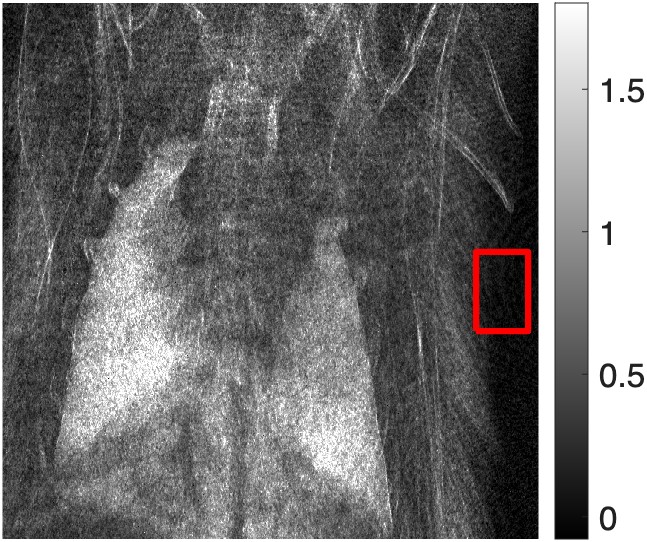

Figure 4: (a) Attenuation, (b) differential-phase, and (c) dark-field images taken with a TLI of a euthanized mouse, calculated using the nominal phase steps. The variance was calculated in the region of interest for each image and compared between the images calculated with the nominal phase steps and corrected phase steps.

Figure 5: (a) Attenuation, (b) differential-phase, and (c) dark-field images taken with a TLI of a euthanized mouse, calculated using the iterative method with 1 harmonic. The variance was calculated in the region of interest for each image and compared between the images calculated with the nominal phase steps and corrected phase steps. It was found that the variance was significantly (α=0.05\alpha=0.05) lower for the corrected phase steps than the nominal phase steps in both the attenuation (p<0.001)p<0.001) and dark-field (p=0.0034p=0.0034)